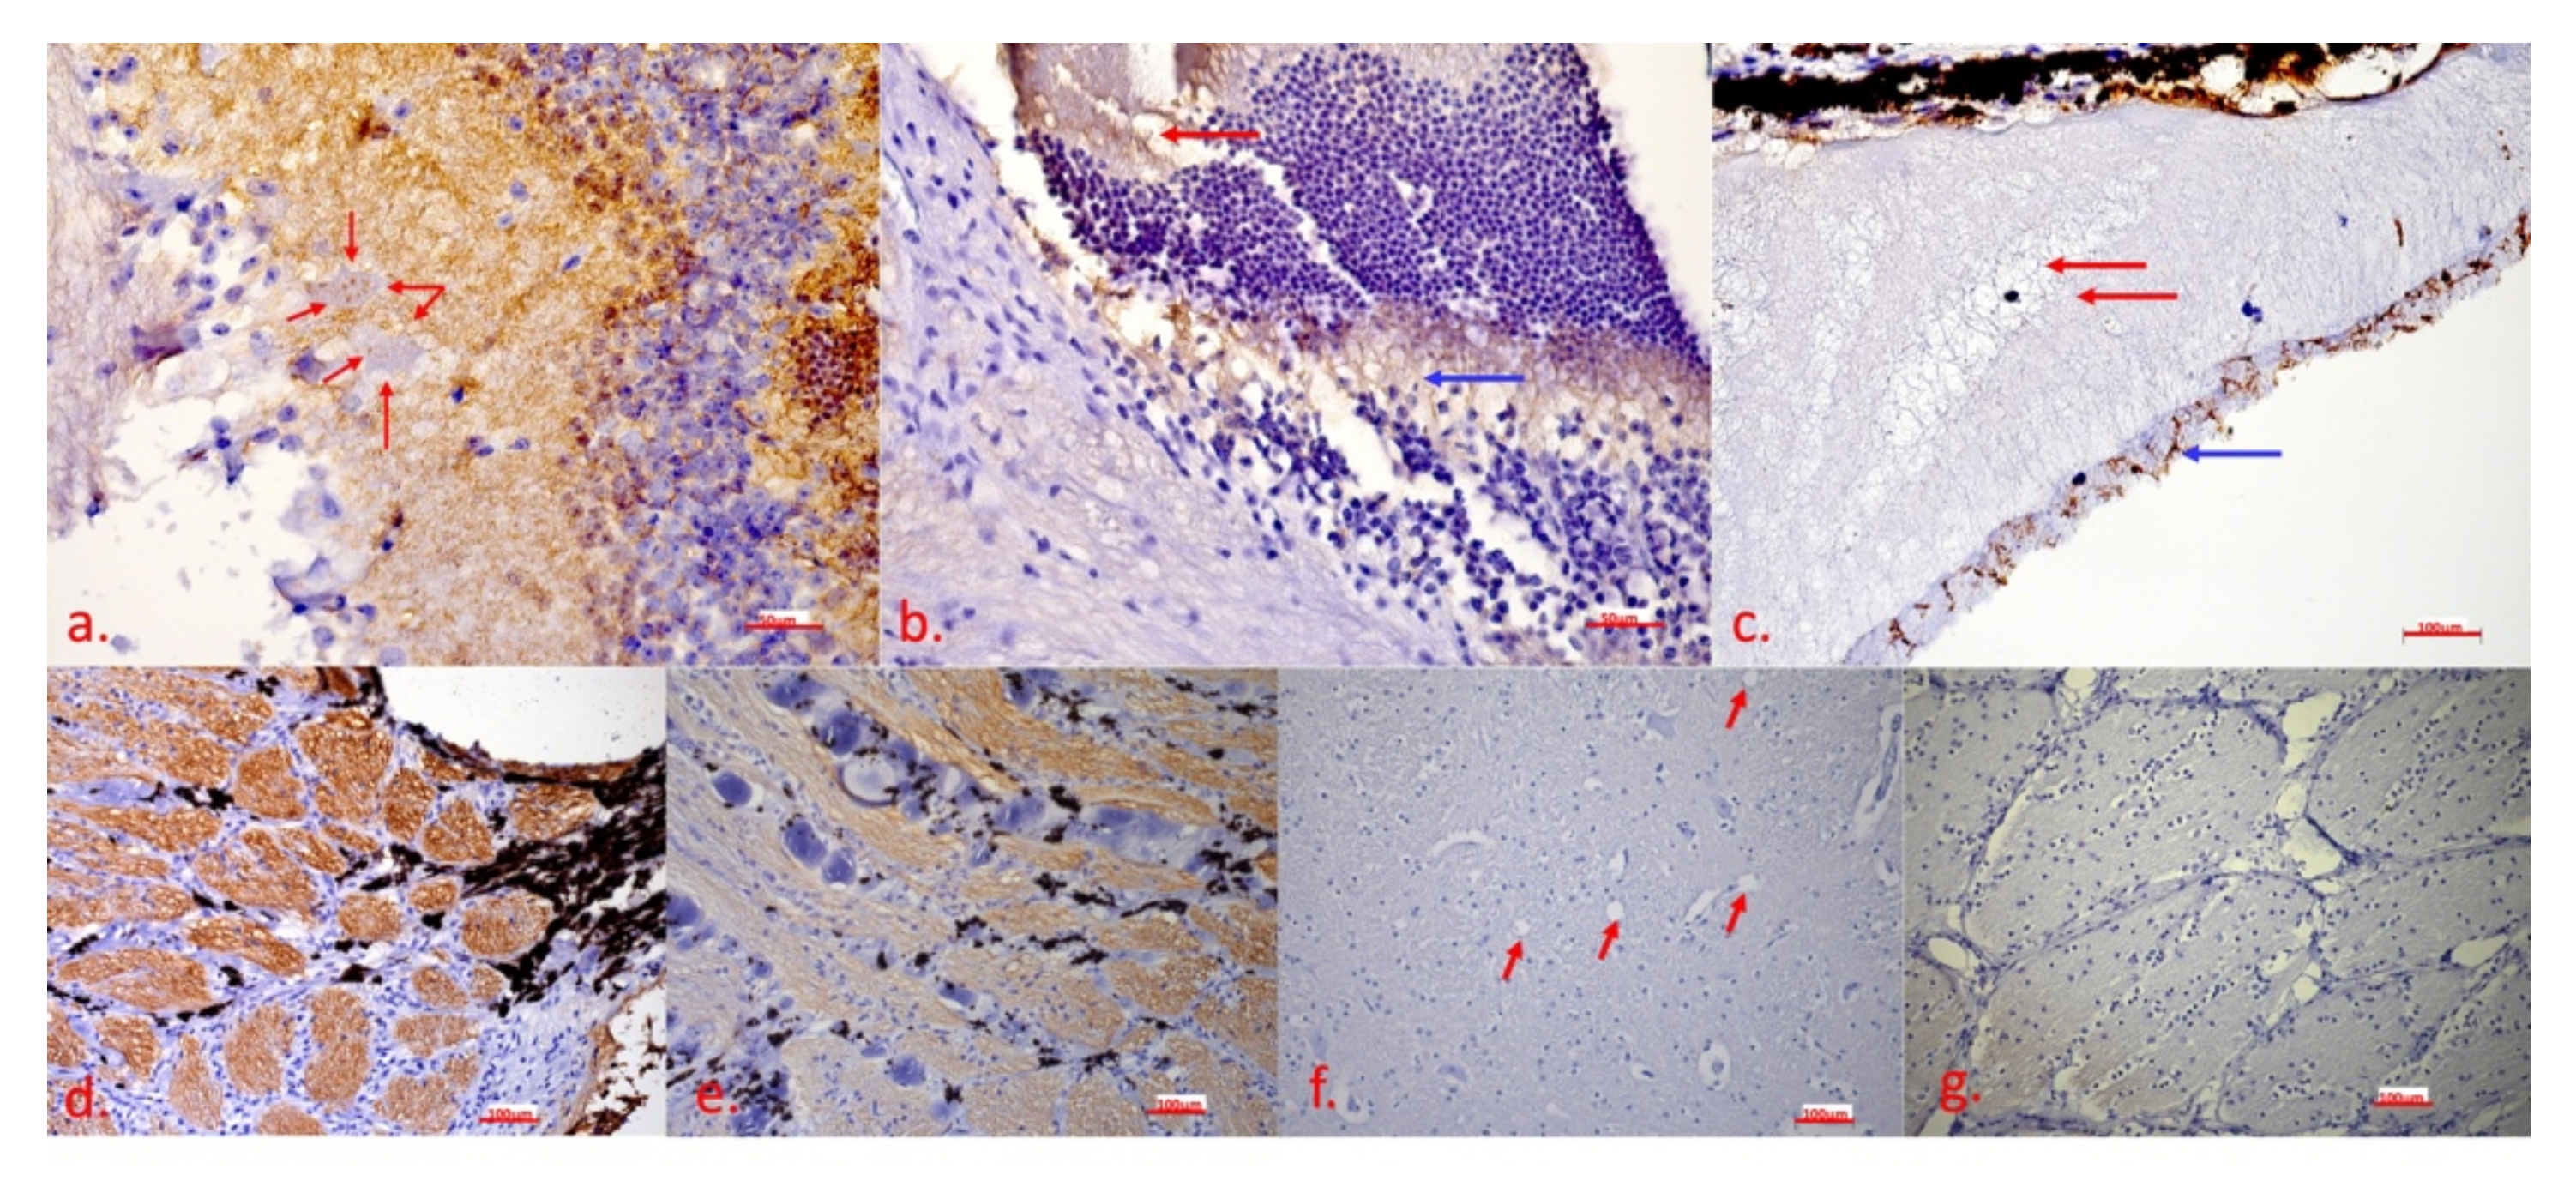

2.2. Clinical and Histopathological Examinations